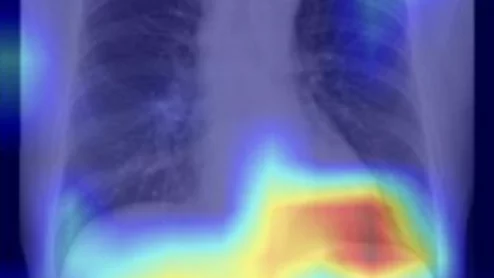

The Nashville, Tennessee, company—which offers AI to monitor radiology reports for unexpected findings—has reached a deal to buy Thynk Health for an undisclosed sum.